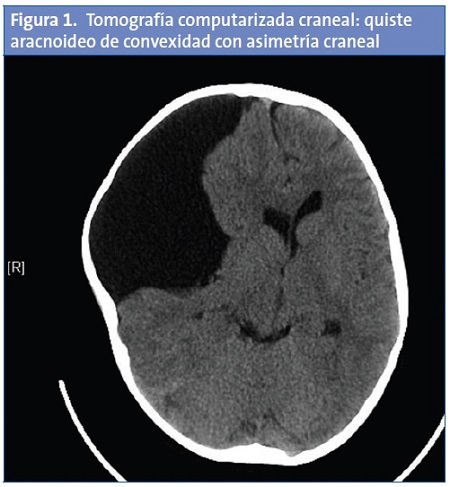

En la TC craneal se visualiza un QA de gran tamaño en la fosa craneal media derecha con desplazamiento de la línea media y colapso de las astas ventriculares adyacentes (Fig. 1), que se confirma en RM craneal mostrando en la región frontoparietotemporal derecha un contenido hipointenso en secuencias de T1 e hiperintensas en T2; que no se modifica tras el contraste con gadolinio (Fig. 2).

En los quistes asintomáticos de convexidad es muy frecuente la remodelación craneal, traduciéndose como asimetría craneal en la TC craneal, como sucedió en nuestro paciente.